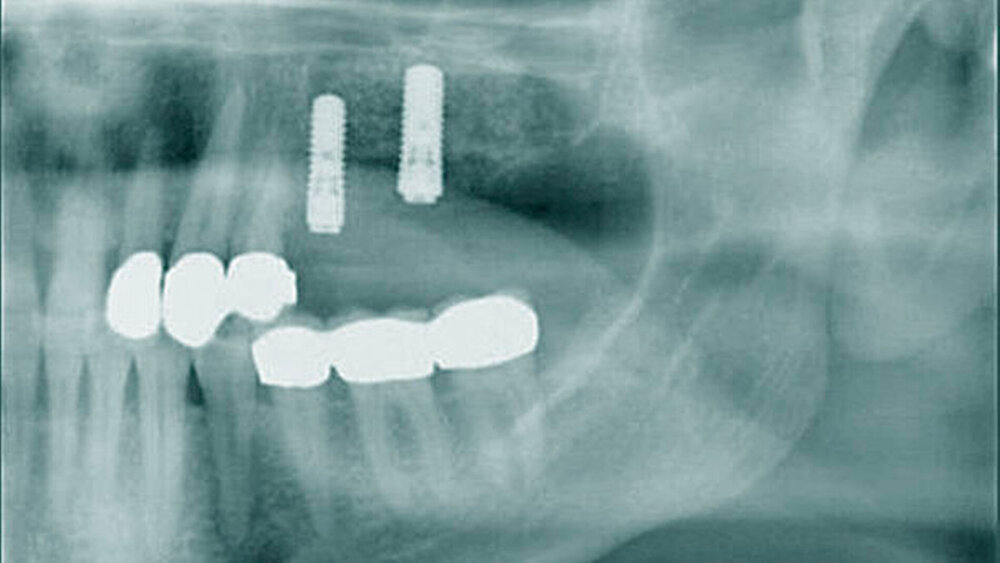

• Patienten mit schlecht eingestelltem Diabetes mellitus scheinen eine verzögerte Osseointegration nach der Implantation aufzuweisen. Nach einem Jahr scheint es jedoch keinen Unterschied in der Implantatstabilität zwischen Diabetikern und gesunden Personen zu geben, auch nicht bei schlecht eingestelltem HbA1c.

• Die Überlebensraten von Implantaten zeigen bei Diabetikern in Studien von bis zu sechs Jahren keine signifikanten Unterschiede zu Nicht-Diabetikern, in einem Beobachtungszeitraum bis zu 20 Jahren ist eine reduzierte Implantat-Überlebensrate bei Diabetikern erkennbar.

• In der Literatur finden sich keine Hinweise darauf, dass Augmentationsverfahren wie guided bone regeneration und Sinuslift eine höhere Komplikations- und Fehlerrate bei Patienten mit gut eingestelltem Diabetes mellitus aufweisen.